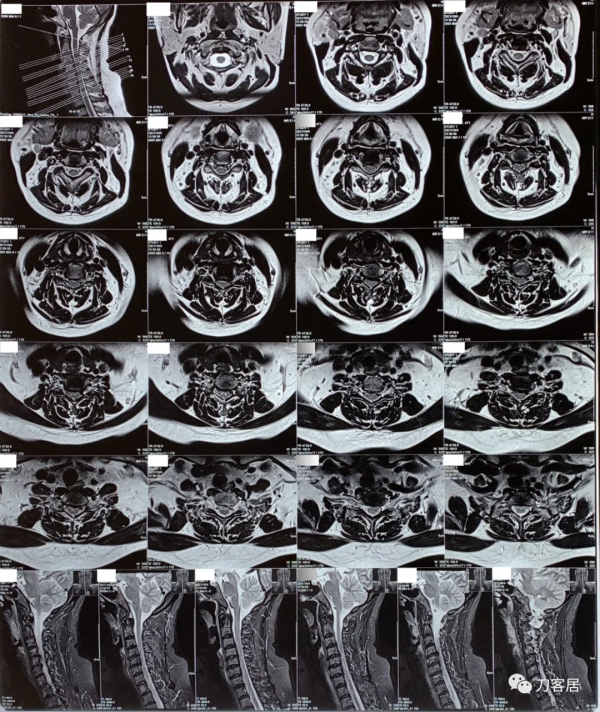

圖9. 20211004頸椎MRI矢狀面T2相及橫截面。提示頸4-5,頸5-6,頸6-7椎間盤突出,椎管狹窄,脊髓訊號改變。

圖10. 20211004頸椎MRI矢狀面T2相及橫截面。提示頸4-5,頸5-6,頸6-7椎間盤突出,椎管狹窄,脊髓訊號改變。

圖11. 20211004頸椎MRI矢狀面T2相,提示頸4-5,頸5-6,頸6-7椎間盤突出,椎管狹窄,脊髓訊號改變。

圖12. 20211004頸椎MRI矢狀面T2相,提示頸4-5,頸5-6椎間盤突出,椎管狹窄,脊髓訊號改變。此兩間隙應該是責任間隙。也應存在頸4-5,頸5-6之間的不穩。

圖13. 20211004頸椎MRI矢狀面T1相,提示頸4-5,頸5-6椎間盤突出,椎管狹窄,脊髓訊號改變。此兩間隙應該是責任間隙。也應存在頸4-5,頸5-6之間的不穩。

圖14. 20211004頸椎MRI矢狀面T1相,提示頸4-5,頸5-6椎間盤突出,椎管狹窄,脊髓訊號改變。此兩間隙應該是責任間隙。也應存在頸4-5,頸5-6之間的不穩。

圖15. 20211004頸椎MRI矢狀面T2相及橫截面。提示頸4-5,頸5-6,頸6-7椎間盤突出,椎管狹窄,脊髓訊號改變。

圖16. 20211004頸椎MRI橫截面。